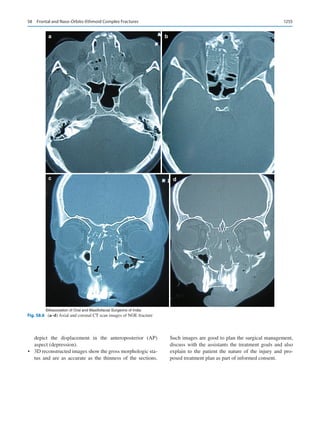

58

Frontal and Naso-Orbito-Ethmoid Complex Fractures��������������������������������������� 1251

Kannan Balaraman